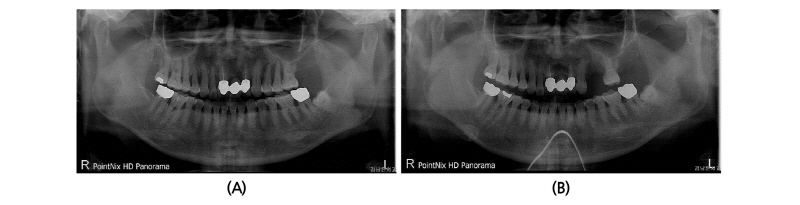

만 53세 여성환자가 #24, 25의 동요도와 불편함을 주소로 내원하였다. 파노라마 촬영과 치주낭측정 후 국소적으로 심한 골결손을 동반한 만성치주염으로 진단하였고, 치석제거와 치근활택술을 시행하고 교합성 외상을 보이는 #24, 25치아의 교합 조정술을 시행하였다. 4주 정도 재평가 기간 후에 동요도가 줄어들지 않고 환자의 불편감이 심해져 #24, 25의 발치를 결정하였다(Fig. 1).

57세의 여성 환자가 상악 좌측부위 시린 증상을 주소로 내원 하였다. 파노라마 촬영과 구강 내 검진 결과 #26의 보철물 하방의 우식이 관찰 되었고 #22, 23-26의 브릿지를 제거한 결과 #26의 우식이 심하여 발치가 추천되었다(Fig. 5A).

발치 후 7주후 임플란트 식립을 위하여 환자가 재내원하였다. 재촬영한 파노라마 상에서 #26부위의 상악동의 함기화가 빠르게 진행되어 상악동 거상술과 골이식술이 필요하게 되었다. 예상과 달리 임플란트 식립을 위한 판막 형성 후 #24, 25 부위에 임플란트 식립이 불가능할 정도의 좁은 치조제가 관찰 되었으며 #26부위도 빠르게 치조제의 흡수가 관찰되었다(Fig. 5B-5D).